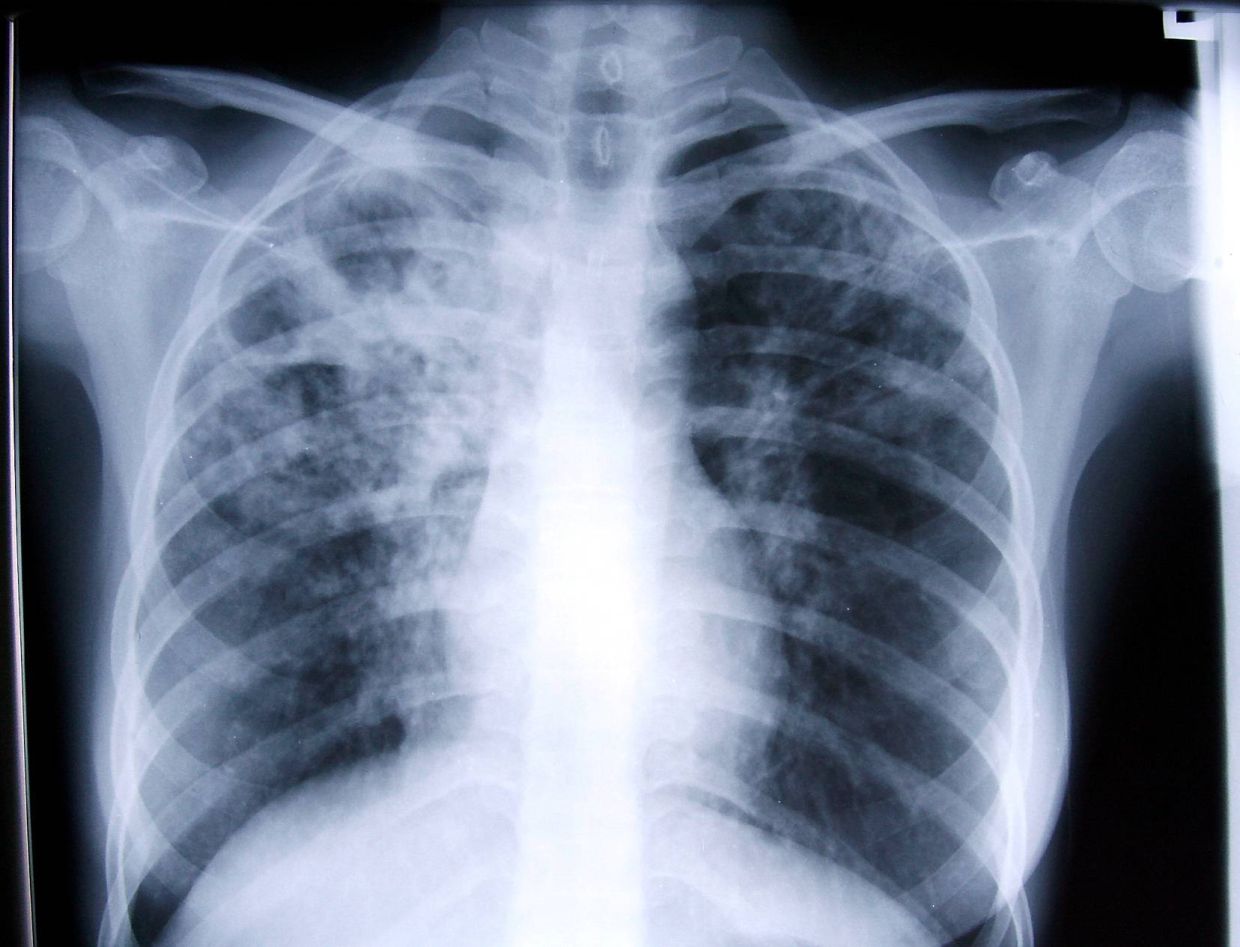

Human Writes: Keeping track of TB in our midst Read full story